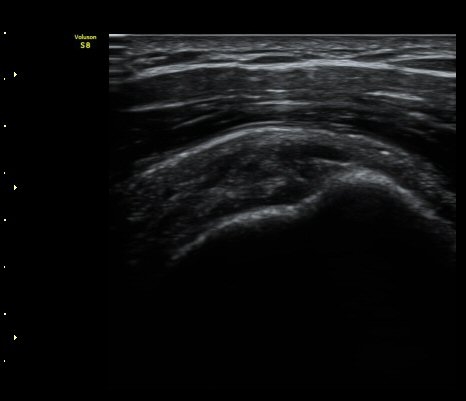

°ß°©ÇÏ±Ù°Ç Á¾´Ü¸é°Ë»ç¿¡¼­ ƯÀÌ ¼Ò°ß ¾øÀ½

(no specific abnormal findngs with longitudinal scan of subscapularis tendon) »çÁø 3